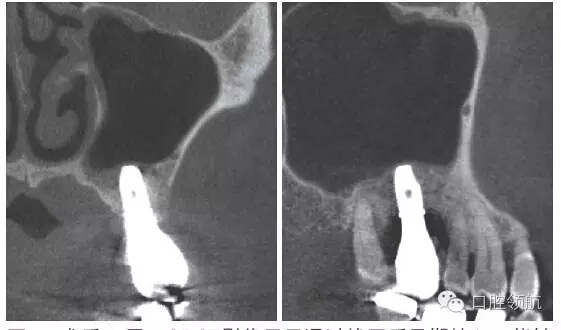

患者,78歲,男性 ,因6 牙齦腫脹來院,檢查見牙根周圍因牙槽骨缺損表現為透過影像(圖1)。在制訂治療計劃時,對于因重度牙周炎、慢性根尖周炎、牙根折斷等原因導致的牙齒缺失需要行上頜竇底提升術的病例,不能單純考慮缺牙區,要同時考慮鄰牙狀態,并用CBCT確認上頜竇底黏膜是否有增厚,這是非常重要的。該病例,根據CBCT能夠觀察到上頜竇底黏膜增厚,拔牙即刻植入感染幾率較高。計劃拔牙后4~8周,拔牙窩牙齦上皮愈合但拔牙窩未消失時(拔牙后早期植入)植入種植體(圖2)。

圖1 CBCT影像確認是由6 引起的上頜竇底黏膜增厚。